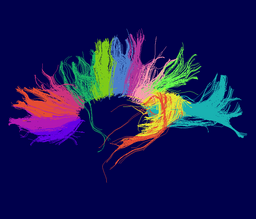

In the past, we have demonstrated ways to characterize the strength of connectivity between selected regions in the brain based on several alternative ways to integrate local diffusion tensor measurements into a global field that provided connection strength estimates for distant points. Our current work aims to provide structural description of the white matter as partitioned into coherent fiber bundles and clusters.

We are developing tools in the 3D Slicer for automatic clustering of tractographic paths through diffusion tensor MRI (DTI) data. By grouping tractographic paths based on shape and location, the white matter architecture may be more clearly visualized, and interesting properties of the clusters (such as for example FA or Westin's linear measure) may be quantified.

Our implementation uses spectral clustering, a method for grouping data using eigenvectors of a data affinity matrix. This image gives an overview of the method. On the left example input tractographic paths are shown (these were created by manually seeding in the 3D Slicer). The center image shows an embedding of the tracts as points in 2D, where the distance between points is related to their shape similarity. This embedding was calculated as an intermediate step during spectral clustering. The image on the right shows the final output in the 3D Slicer, where tractographic paths are colored by cluster membership.

Atlas creation and automatic labeling has been performed in high-quality DTI datasets from Susumu Mori. Images showing example segmentation results are below. Work is underway to apply this atlas to segment additional datasets to define regions of interest that may be used in the study of schizophrenia.

Selected anatomical regions, automatically labeled using the cluster atlas in 3 subjects.

Subdivisions of the corpus callosum, labeled using the cluster atlas in 3 subjects.